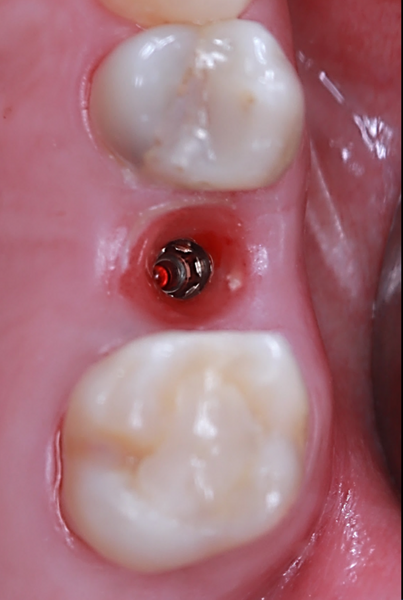

To preserve the ridge contour over time, cerabone plus was hydrated according to the manufacturer’s instructions and placed into the buccal gap at site #25 (Figs. 10a–f). Both sites received healing abutments and were sutured using mesial and distal single interrupted sutures to ensure soft-tissue stability during the healing phase (Figs. 11a–f & Figs. 12a–d). The patient received postoperative instructions along with an analgesic prescription and was scheduled for suture removal after two weeks.

After 60 days, the patient returned to the clinic for intra-oral scanning to initiate the definitive crown workflow. A noteworthy advantage of the Straumann Anatomic Healing Abutment XC is that it allows direct scanning without removal, eliminating the need for a scan body. This significantly minimises soft-tissue disturbance, enhances patient comfort and reduces overall chair time.